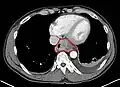

Additional testing is needed to assess how much the cancer has spread (see #Staging, below). Computed tomography (CT) of the chest, abdomen and pelvis can evaluate whether the cancer has spread to adjacent tissues or distant organs (especially liver and lymph nodes). The sensitivity of a CT scan is limited by its ability to detect masses (e.g. enlarged lymph nodes or involved organs) generally larger than 1 cm.[41][42] Positron emission tomography is also used to estimate the extent of the disease and is regarded as more precise than CT alone.[43] Esophageal endoscopic ultrasound can provide staging information regarding the level of tumor invasion, and possible spread to regional lymph nodes.

Contrast CT scan showing an esophageal tumor (axial view)